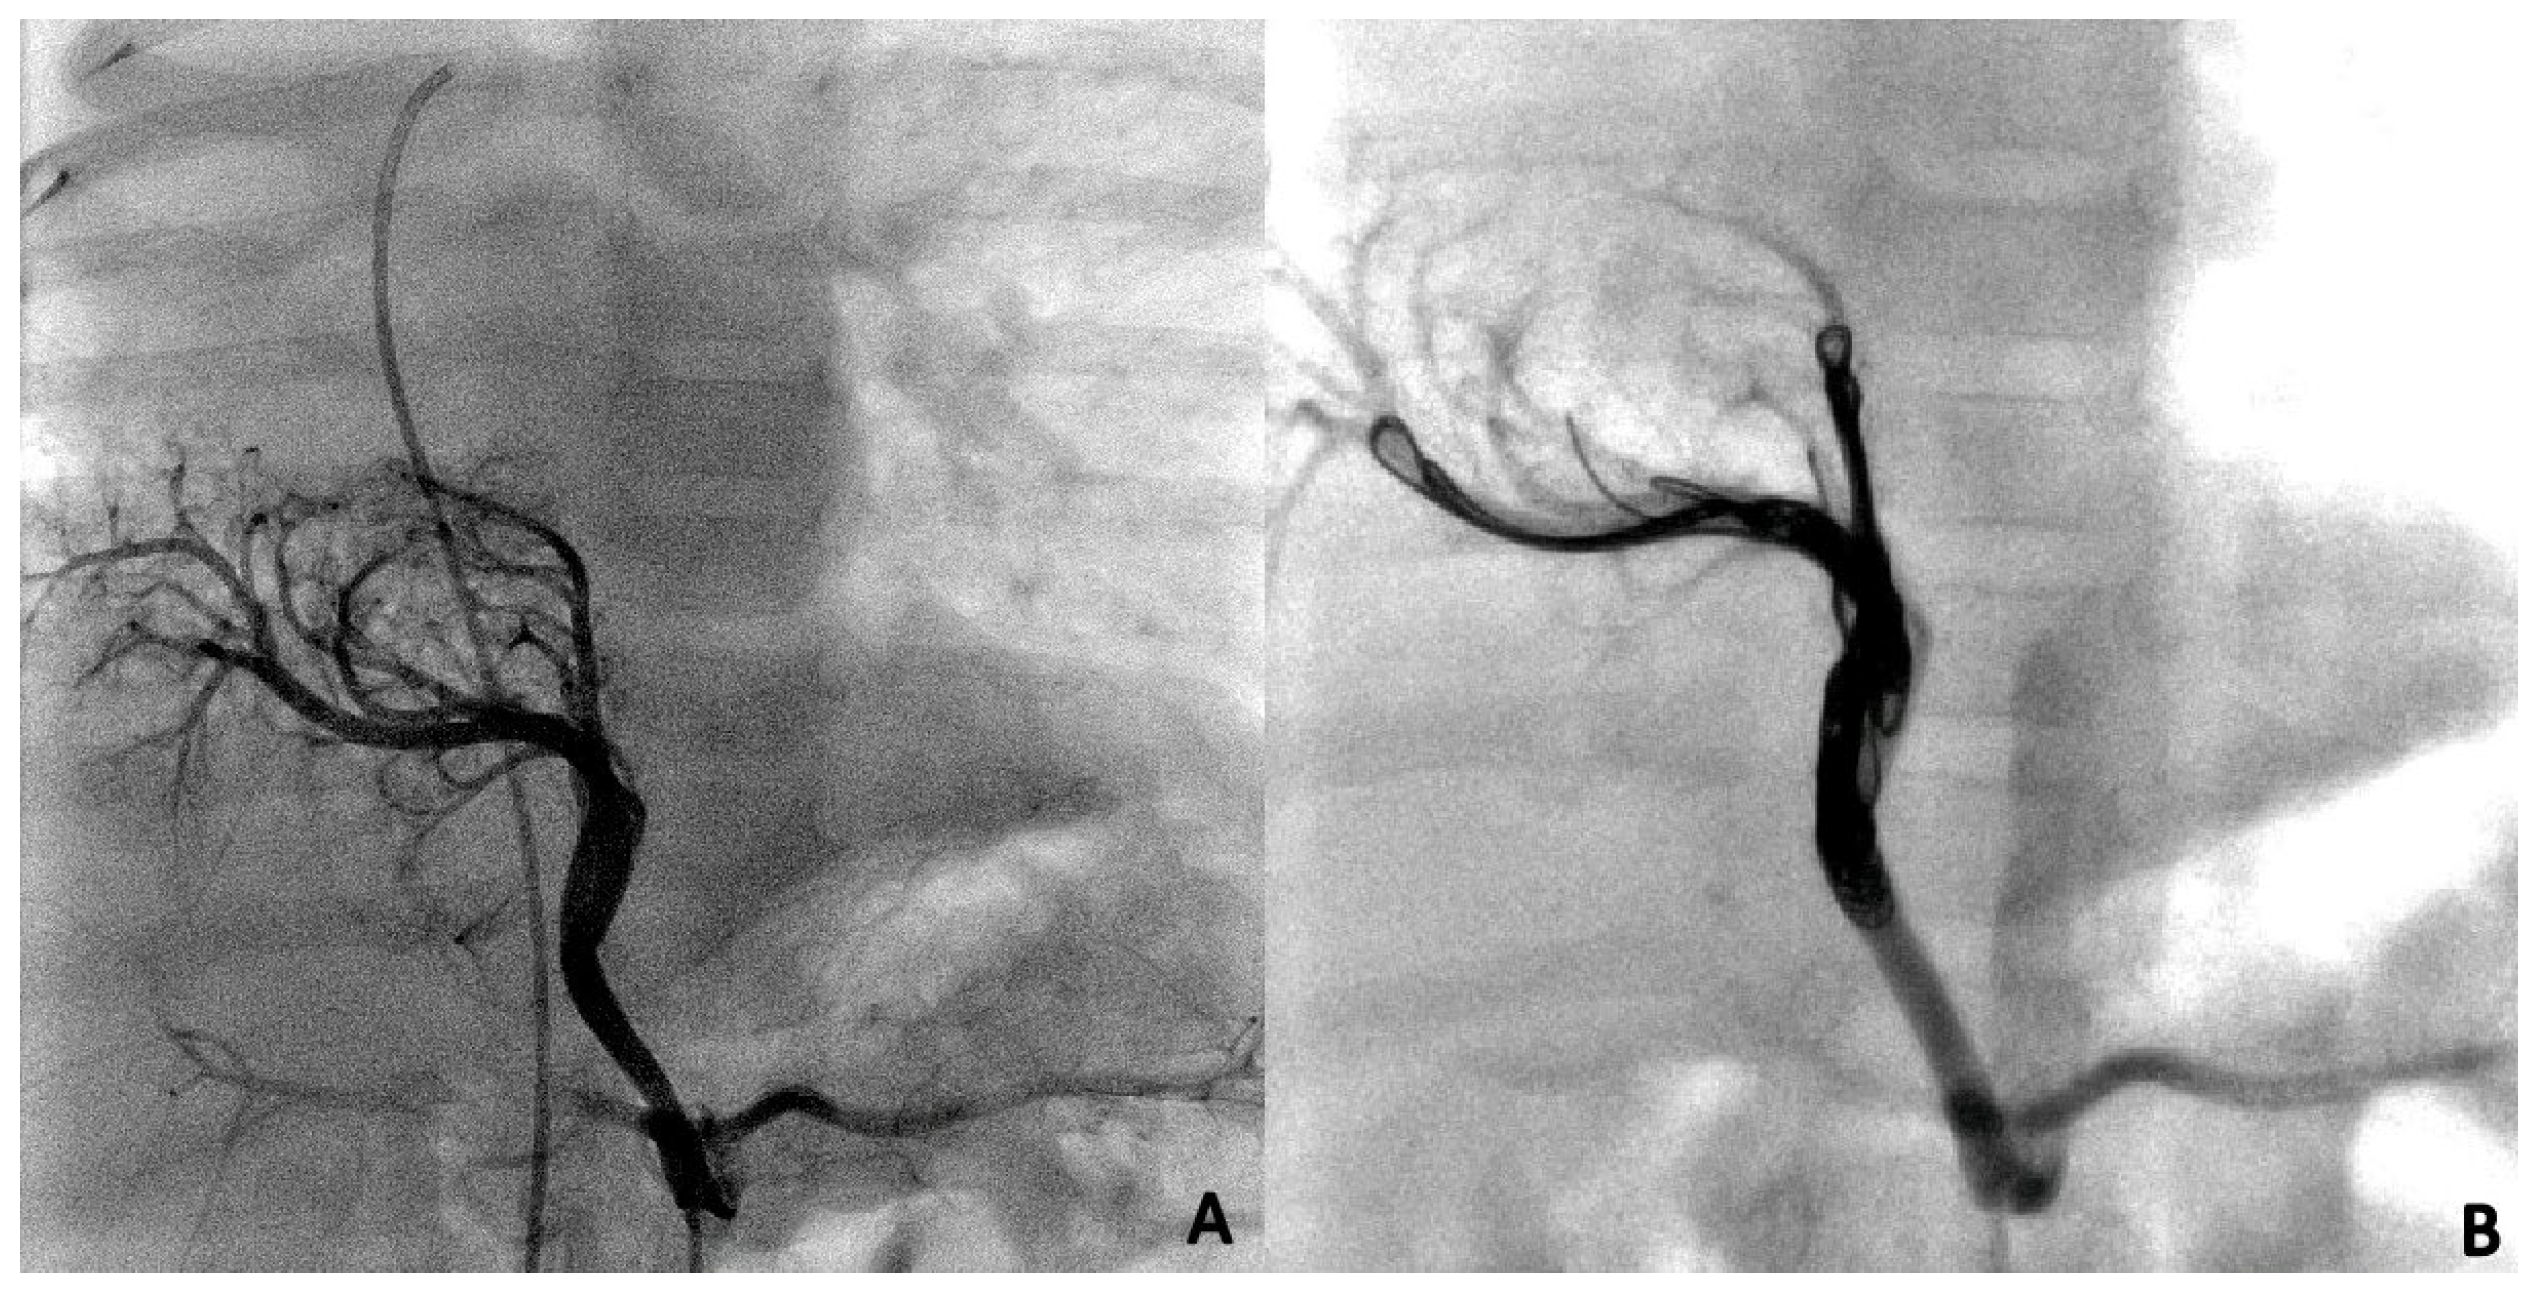

3.3. Endovascular Embolization

During the first procedure, 47/71 (66.2%) patients underwent endovascular embolization of the PS feeding vessel (Figure 1, Figure 2 and Figure 3). The type and number of occluder vascular devices are detailed in Table 3. In 14/47 (36.2%) patients, occlusion was achieved with a combination of vascular plugs and micro coils (Figure 1, Figure 2 and Figure 3). Reasons for non-embolization or delayed embolization are also described in Table 3. In 21 cases, the feeding vessels were too small or without hemodynamic significance. The feeding vessels were too large for endovascular treatment (no suitable device available on the market at the time of catheterization) in two patients (Figure 4), and one patient was hemodynamically unstable, leading to abortion of the embolization procedure. One coil migrated and was recaptured by snare. One patient experienced transient atrioventricular block during right heart catheterization. Procedure time and radiation exposure are detailed in Table 3. The median hospital stay was 3 days (IQR, 2–8).

Figure 4. Large vessel, not suitable for endovascular treatment, at time of procedure.